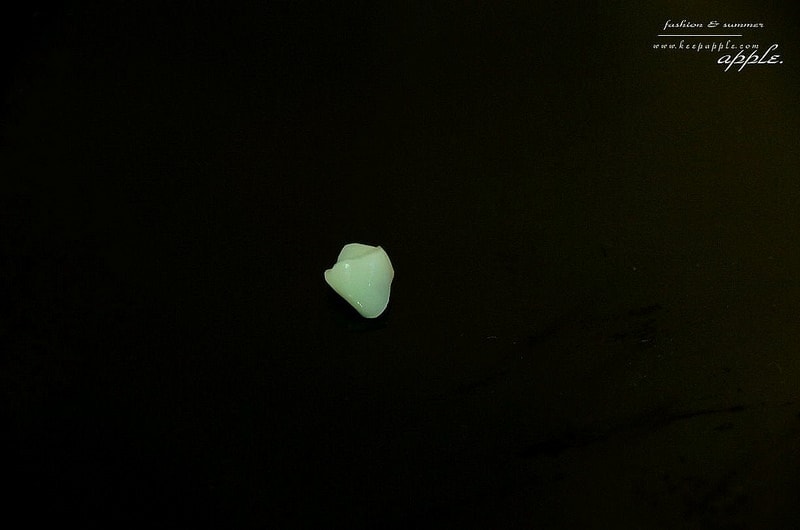

我選的材質是很好的玻璃陶瓷

而且因為是三色的設計仿真度很高

當場就可以把假牙研磨出來囉!

然後會再由牙技師進行更細緻的上色

上完色後會再進行超高溫烤爐烘烤定色

完成的牙套就是這樣

接著裝到牙齒上由醫師進行固定的動作

裝假牙的動作就完成了

是不是超級快的!

所以才會說看一部電影的時間就可以把假牙給做好